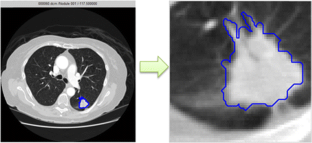

Fig. 1